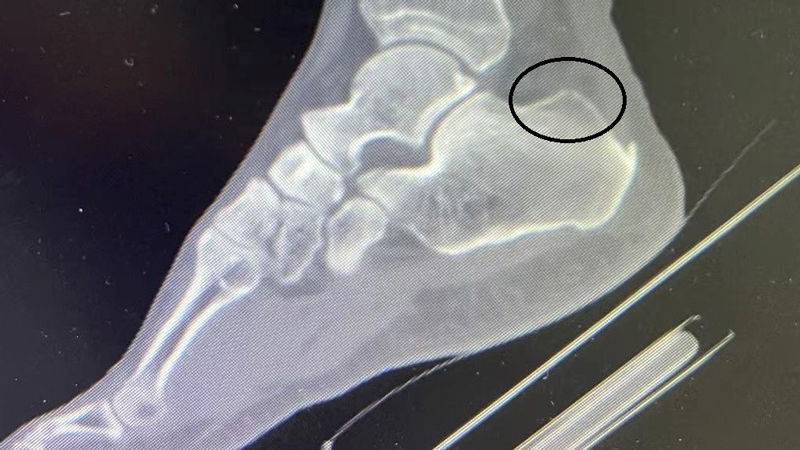

术前可见跟骨后上结节异常骨性凸起(Haglund畸形)

术后复查畸形消失